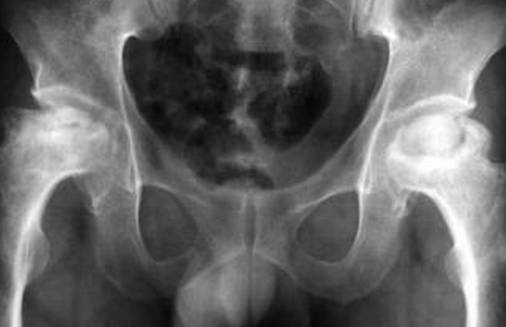

所谓股骨头坏死就是某些致病因素使骨结构破坏,骨组织营养中断,骨细胞凋亡,骨小梁破坏,即发生骨坏死。坏死是在无菌条件下发生的,故称无菌性坏死。发生在股骨头部位称股骨头无菌性坏死,简称股骨头坏死。

骨坏死可发生在人身体的很多部位,而股骨头坏死最常见,这与股骨头特殊的生理功能和结构密切相关,髋关节是人体六大关节中最大的球窝关节,它偏心承重、受力复杂、活动范围广,应力集中,故股骨头易发生坏死。

股骨头坏死以髋关节疼痛,跛行为主要临床表现。早期可以没有任何临床症状,而是在拍摄CT片或X线片时发现,也可以最先出现膝关节疼痛。在髋部又以内收肌痛(大腿根痛)出现较早。疼痛可呈持续性或间歇性,如双侧病变可出现交替性疼痛。